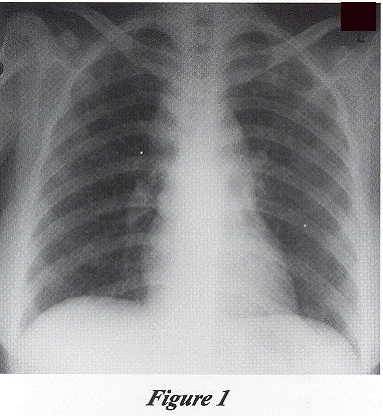

CXR (Figure 1) showed fine mottling shadows in both lower zones.